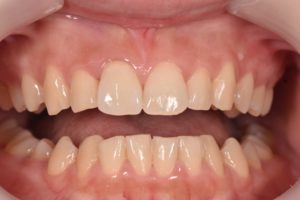

術前

年齢:19歳

主訴:前歯の見た目が気になる

詳細:前肢の審美障害を主訴に来院された患者さんです。上の前歯に過去に治療し不適合となったクラウンが入っており、その横の歯に欠けた跡がみられました。不適合のクラウンのみをやりかえると左右中切歯の幅がかなり差が生じてしまうことから、欠けている部分をダイレクトボンディングにて形態修正を行い、不適合クラウンはジルコニアセラミックで再治療することで審美障害を改善しました。